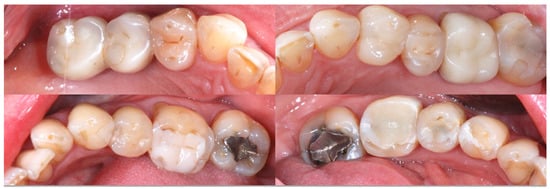

2.2. Clinical Example

2.3. Outcome Achieved